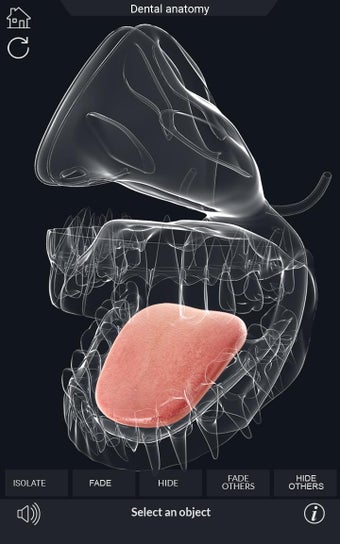

Esta aplicación es un modelo 3D de los dientes, que contiene muchas partes y muestra las condiciones dentales. Cada parte tiene un nombre y una función. Puedes mover la cámara alrededor del modelo para obtener una vista de 360° de las diferentes partes. Puedes hacer zoom para ver mejor cada parte. También puedes rotar la cámara para obtener una vista diferente del modelo.